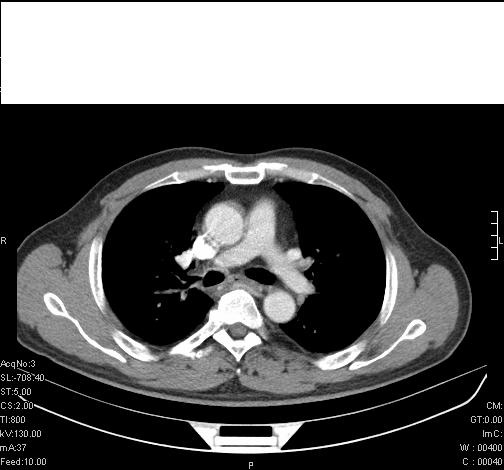

标题: CT6685:右肺阻塞性炎症,增强CT。

前几天,发了患者的平扫片,患者抗炎一周后增强扫描。右中叶病灶吸收明显,但下叶病灶未见明显吸收。右肺门可见结节影,看来凶多吉少

右肺下叶支气管管腔狭窄,管壁增厚,右下肺见斑片状高密度影,考虑右侧肺门中心肺癌伴阻塞性肺炎

右肺下叶支气管壁明显增厚,考虑癌症并阻塞性炎症、肺门淋巴结肿大

考虑右肺癌并阻塞性炎症、肺门淋巴结肿大

还是考虑右肺中央型肺癌可能性大

考虑右肺中央型肺癌可能性大

右主支气管狭窄,管壁增厚。考虑右中心性肺ca伴阻塞性肺炎。